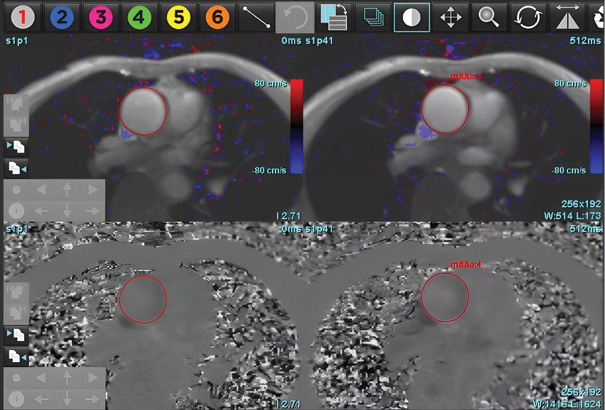

The cine-CMR images were analyzed during routine clinical workflow by using commercial software (syngo.Via). Using the short-axis cine images, the LV and RV end-diastolic and end-systolic frames were identified. In each short-axis slice, the endocardial boundary of the LV and RV were manually delineated. LV and RV papillary muscles and trabecular tissue were included in the blood pool volume. In the LV basal slices, the LV contour was drawn to include the LV outflow tract to the level of the aortic valve cusps (see Figure 1). Contours for the postprocessing of flow study at the level of ascending aorta were drawn by using the manual method, whereas the DL method automatically recognized the aorta, and a contour was formed for all phases (see Figure 2). Simpson’s method of disks was used to calculate the LV Ejection fraction, as well as end-diastolic and end-systolic volumes (EF, EDV and ESV). These values were then reported and recorded. We divided the patient cohort into three clinically relevant groups: severely reduced LVEF (≥ 35%), mildly to moderately reduced LVEF (35–50%), and normal LVEF (≥ 50%). MR was classified as Mild (< 30ml), Moderate grade II (30–44ml), Moderate Grade III (45–59ml), and severe (> 60ml) for SW1, SW2, and echocardiography.

The DL-EF, SV, EDV values were determined from cine short-axis images by using fully automated commercially available algorithms: SuiteHeart, Neosoft, Pewaukee, Wisconsin, USA. The vendor provided virtual training of how to optimally use the software. A single user was trained to use both software packages. Fully automated segmentation was then performed without any user input. The automatically and manually generated LVEDV, LVESV, AoF (Aortic forward flow), PG (Pressure gradient at LVOT) and LVEF were recorded (see Figure 3: A, B, C).

Aortic forward flow and regurgitation was calculated by using DL and the manual segmentation method. Analysis of pressure gradient at the level of LVOT was performed. MR was calculated by using the indirect method for both types of software (MR=LVSV-Aortic forward flow).